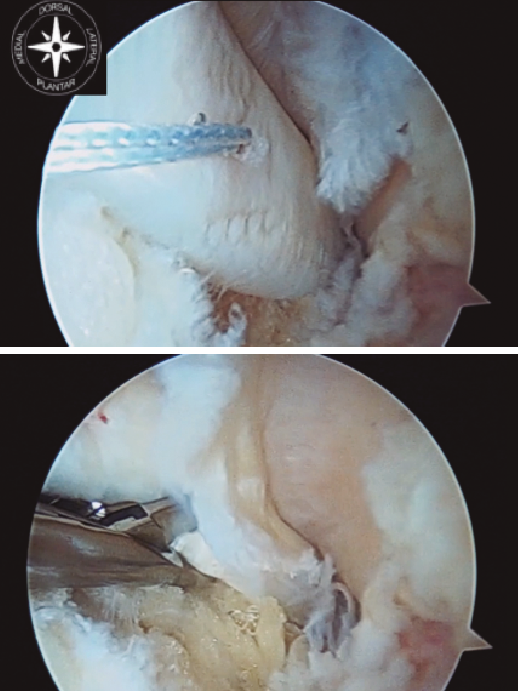

Figura 1. Identificación, desbridamiento y tracción con vessel loop del tendón flexor hallucis longus (FHL). A: FHL; B: astrágalo; C: calcáneo.

Una vez identificado el FHL, es importante realizar un correcto desbridamiento del túnel osteofibroso por donde discurre, para así poder obtener la mayor cantidad posible del mismo. Recomendamos dar una sutura en el tendón FHL, o alternativamente usar una pinza artroscópica, para traccionar del mismo y así poder obtener tendón FHL incluso de zona 2 (Figura 1).

Figura 2. Tracción del tendón flexor hallucis longus (FHL) y sección del mismo en la zona 2, con flexión de la primera metatarsofalángica y tobillo.

La longitud mínima ideal del tendón FHL para la transposición en el calcáneo es de 15 mm. Cuando se realiza el corte del FHL con la tijera artroscópica, se debe flexionar el tobillo y la primera metatarsofalángica para obtener la máxima longitud posible y a su vez proteger el paquete neurovascular (Figura 2).

Una vez seccionado el tendón, se saca a través del portal posteromedial y se realiza una sutura de refuerzo de tipo Krakow y medimos el tamaño de la plastia (Figura 3).

Figura 3. Obtenemos la plastia por el portal posteromedial, se realiza sutura de refuerzo de tipo Krackow y medición de la plastia.